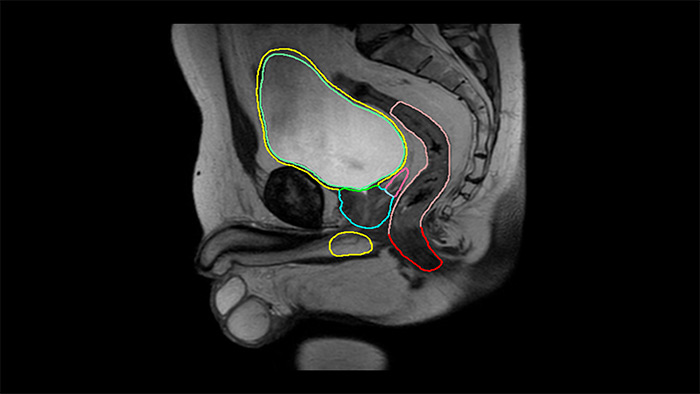

![MR Neuro Imaging]()

Damit mehr Patienten von der Magnetresonanztomographie profitieren, erfahren Sie hier mehr über neue neurologische Anwendungen von Philips Healthcare.